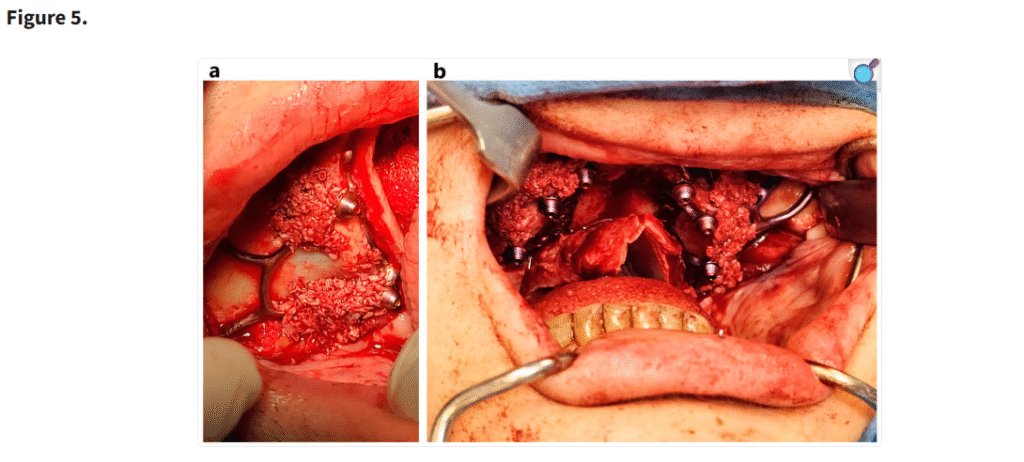

十分な視野が得られた段階で、患者の上顎解剖に正確に適合するように設計されたカスタムサブ骨膜下インプラントを歯槽堤上に配置した(Figure 1)。一部の症例では、歯槽堤が狭く高い場合にテンプレートを用いて骨を削除した(Figure 2・Figure 3)。手術中に頬脂肪体が脱出した場合には、MaIインプラント®(Integra Implants®, ロッジ、ポーランド)の前庭側表面に縫合した(Figure 4)。また一部の症例では、オトガイ部や外斜線から骨片を採取し、MaIインプラントの枝を覆う目的で使用した(Figure 5)。

(a, b) 使い捨てのボーンスクレーパーを用いて骨片を採取し、MaI インプラント®(Integra Implants®, ロッツ〔ポーランド〕)のラミ部に填入した。骨片の目的は、MaI インプラント®の裂開リスクを低減することであった。